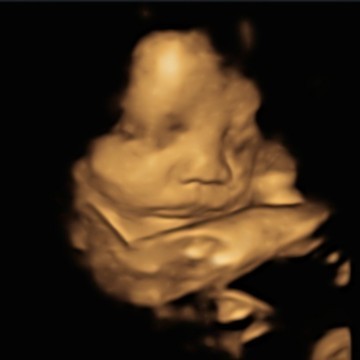

Bund kenapa ya sekarang pinggang aku jadi serba sakit 😭 duduk kelamaan sakit , tidur juga sakit dan buat jalan pun sakit Bun pas bagian ms V kayak linu2 gitu apa itu tandanya Dede bayi udh masukk panggul bund atau mungkin epek mendekati persalinan mohon koment nya bund terimkasih 🙏 #seriusnanya #ingintahu #jangandibully